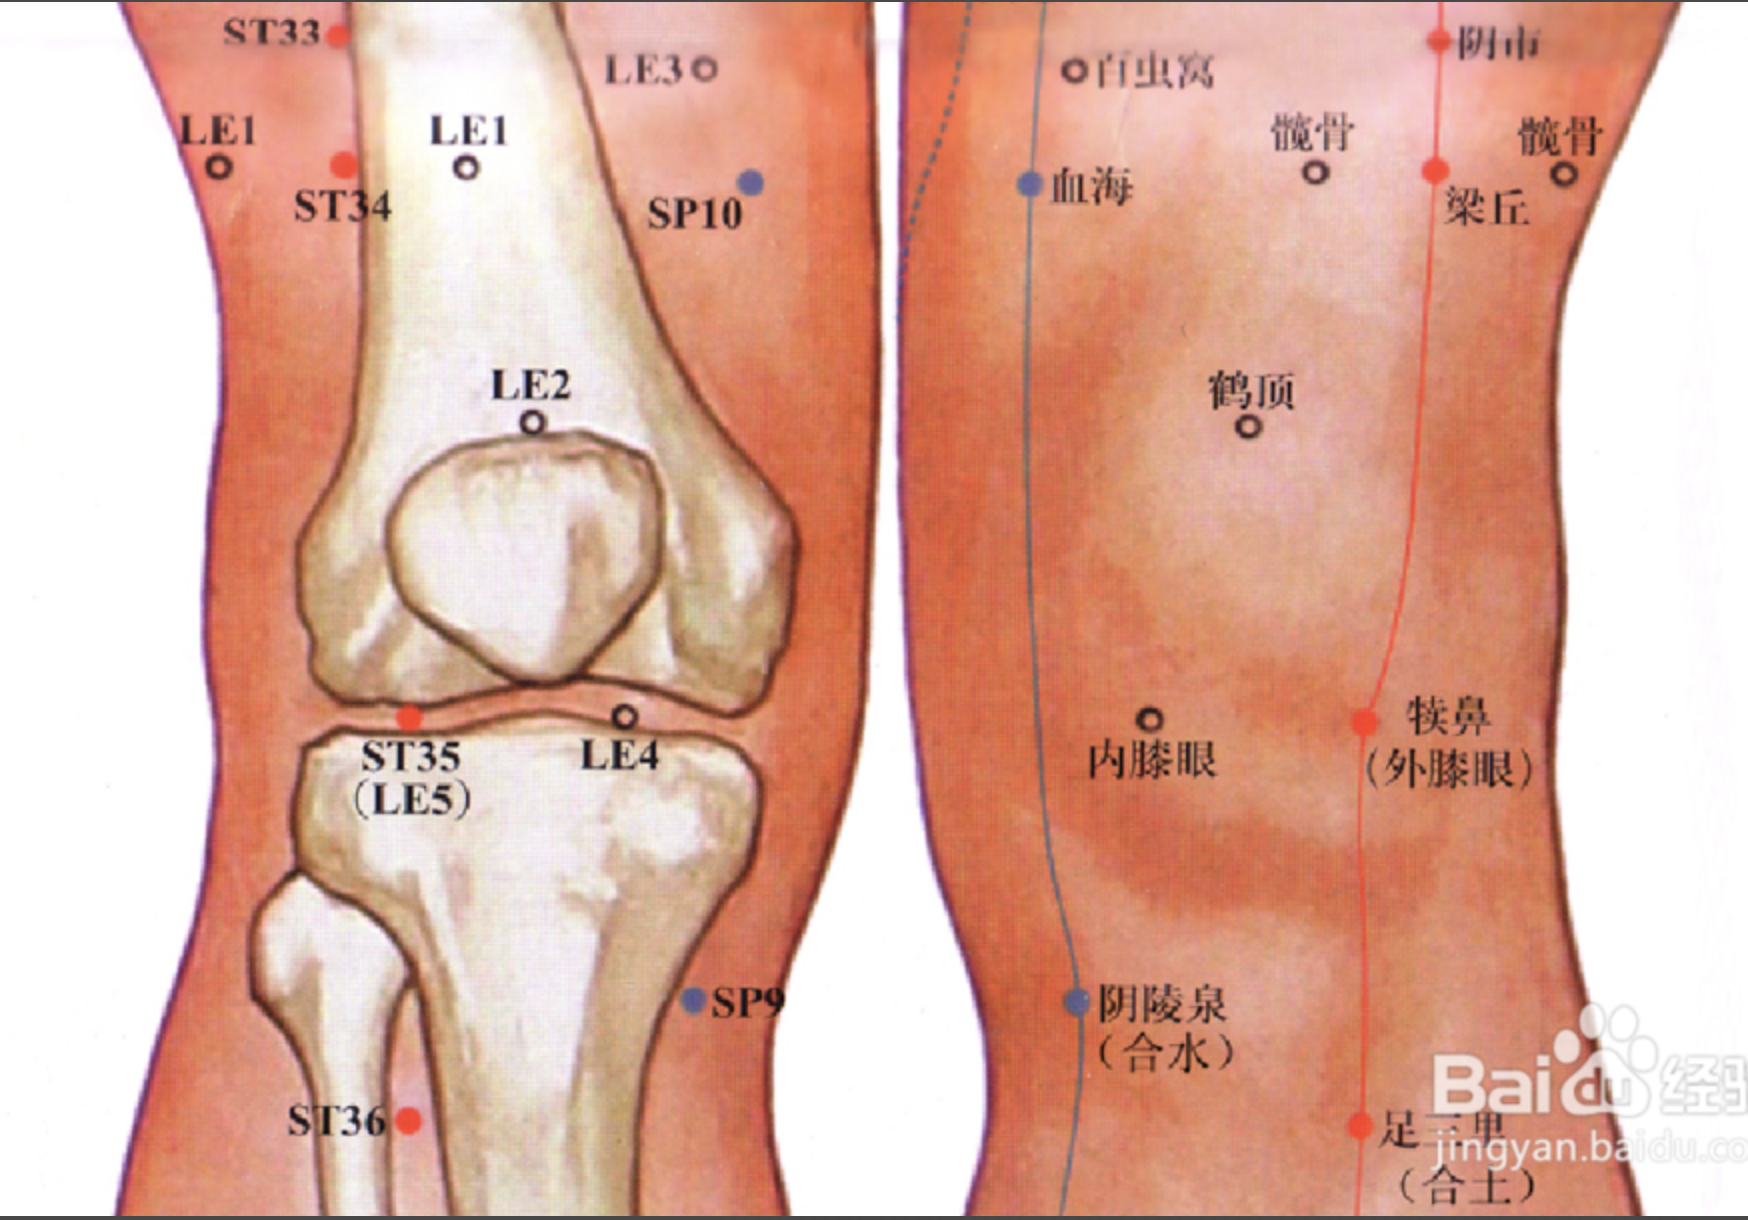

梁丘

【定位】 屈膝,大腿前面,当髂(qià)前上棘(jí)与髌(bìn)骨外上缘的连线上,髌骨上缘 2 寸。

【主治】 膝肿痛,下肢不遂,胃痛,乳痈,血尿。

【配伍】 配足三里、中脘治胃痛。

【刺灸法】 直刺 1 ~ 1.2 寸。

【附注】 足阳明经郗(chī)穴。

足三里

【定位】 在小腿前外侧,当犊(dú)鼻下 3 寸,距胫骨前嵴(jí)外 1 横指(中指)(图 10-21-4)。

【主治】 胃痛,呕吐,噎(yē)膈,腹胀,泄泻,痢疾,便秘,乳痈,肠痈,下肢痹痛,水肿,癫狂,脚气,虚劳羸(léi)瘦。

【配伍】 配中脘、梁丘治胃痛,配内关治呕吐,配气海治腹胀,配膻中、乳根治乳痈,配阳陵泉、悬钟治下肢痹痛,常灸足三里可养生保健。

【刺灸法】 直刺 1 ~ 2 寸,强身健体用灸法。

【附注】 (1)足阳明经所入为“合”;胃的下合穴。(2)本穴有强壮作用,为保健要穴。(3)参考资料:①据报道,针刺健康人和胃病患者的足三里和手三里,观察发现胃驰缓时针刺收缩加强,胃紧张时变为弛缓,并可解除幽门痉挛。②据报道,针刺单纯性消化不良和中毒性消化不良患儿的足三里、合谷、三阴交,可使原来低下的胃游离酸、总酸度、胃蛋白酶和胃脂肪酶活性迅速升高。③据报道,针刺人及家兔的足三里,发现裂解素(主要是裂解素含有大量多糖体的革兰氏阴性杆菌,也能灭活某些病毒)都有增加,人增加 17.85 单位,兔增加 62.1 单位,两者均在针后 12 小时增加最明显。④据报道,针刺家兔的“足三里”“大椎”可使其调理素明显增加,从而促进白细胞吞噬指数的上升,增强其免疫能力。